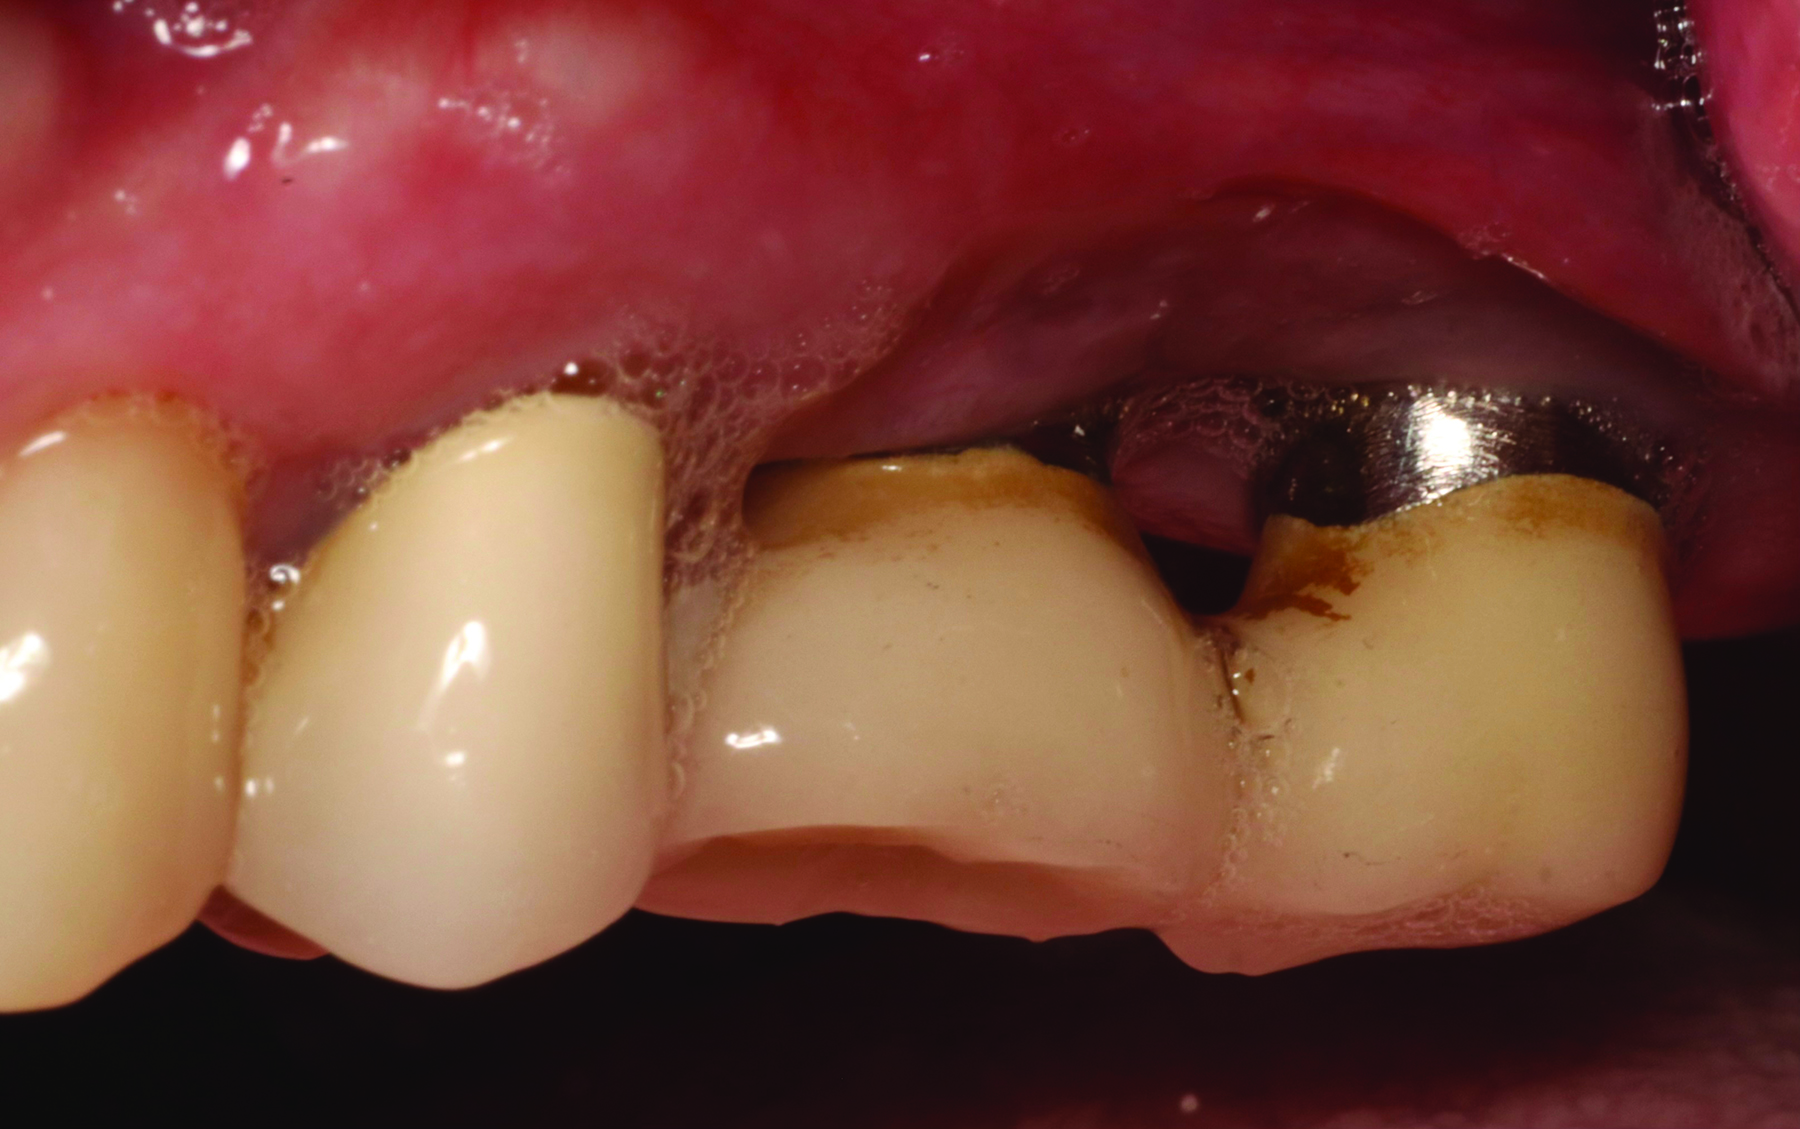

Fig 2. A patient presented with inflammation around implants. The patient was having difficulty brushing the area due to a shallow vestibule, the proximity of the implants, and a lack of keratinized tissue surrounding the implants.

Figure 2